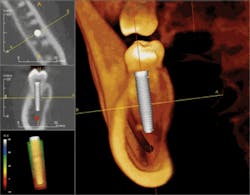

There are many software programs available for CBCT assisted implant surgery. Virtual Implant Placement® (VIP by Implantlogic, Implantlogic.com) and SimPlant (Materialize) are two programs that provide the ability to treatment-plan cases from prosthetically driven scanning appliances, to implant selection and placement, to stealth surgical guide-assisted implant placement. Implant software packages work with most popular implant systems, allowing the selection of the exact implant required, thus reducing the need to overstock expensive implant inventory. There are other proprietary systems which offer CBCT implant planning. The best software is the one that functions for the dentist and the implant system that works best in her/his hands.

Guided-implant placement planning precisely determines the margins of error from vital structures, such as the mandibular nerve, lingual concavities, floor of the nose, facial undercuts, adjacent roots, and the maxillary sinus. CBCT helps surgeons operate within the "zone of safety" and has significantly increased the predictability of 3-D implant placement (Figure 6).

The CBCT scan is uploaded to the planning software and the final implant positions and selections are determined according to sound treatment-planning protocol. Implants are planned 1.5 mm from adjacent teeth and 3 mm from adjacent implants. This helps maintain healthy support bone and papilla adjacent to the implants. The mandibular nerves, adjacent tooth roots, sinuses, and other structures are determined and the case is planned within the desired zone of safety. The implant plan is e-mailed to the laboratory and the scanning appliance is sent back for processing. The laboratory technician and consulting dental surgeon evaluate the plan, and final corrections are made prior to surgical-guide fabrication.